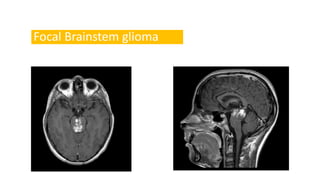

Focal Brainstem glioma

2. Mesencephalic

Includes diffuse, focal, exophytic and tectal variants.

Focal brainstem gliomas are more common here than elsewhere in

the brainstem

Tectal plate gliomas are typically indolent